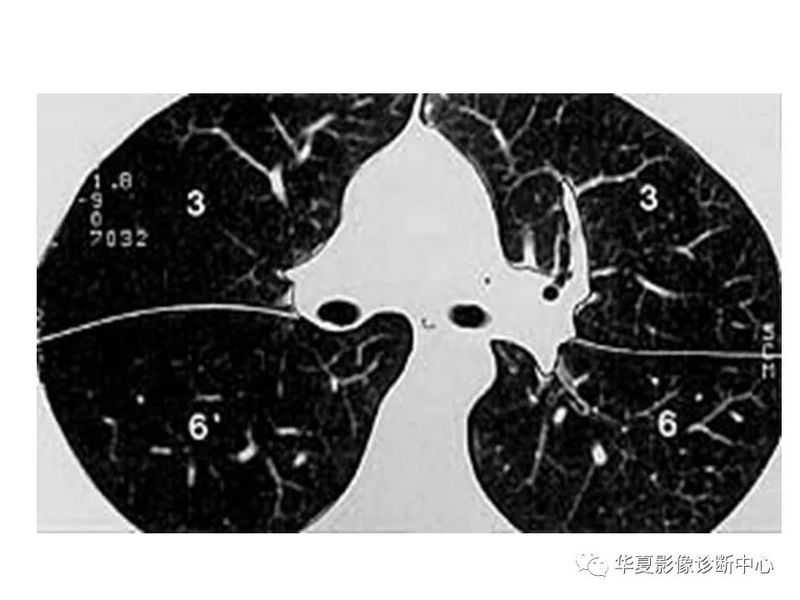

干货 | 汇总胸部CT读片扫盲知识,看懂胸部CT不再难